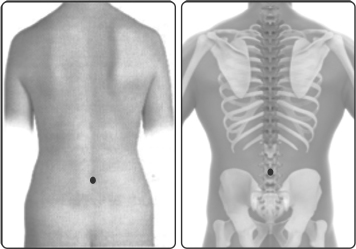

பின்னல்வர்மம், நாபியின் நேர் பின்பாக முதுகெலும்பில் அமைந்துள்ளது. இவ்வர்மம் பின்னெல் வர்மம், வாயுக்காலம் என்னும் வேறுபெயர்களாலும் வழங்கப்படுகிறது.